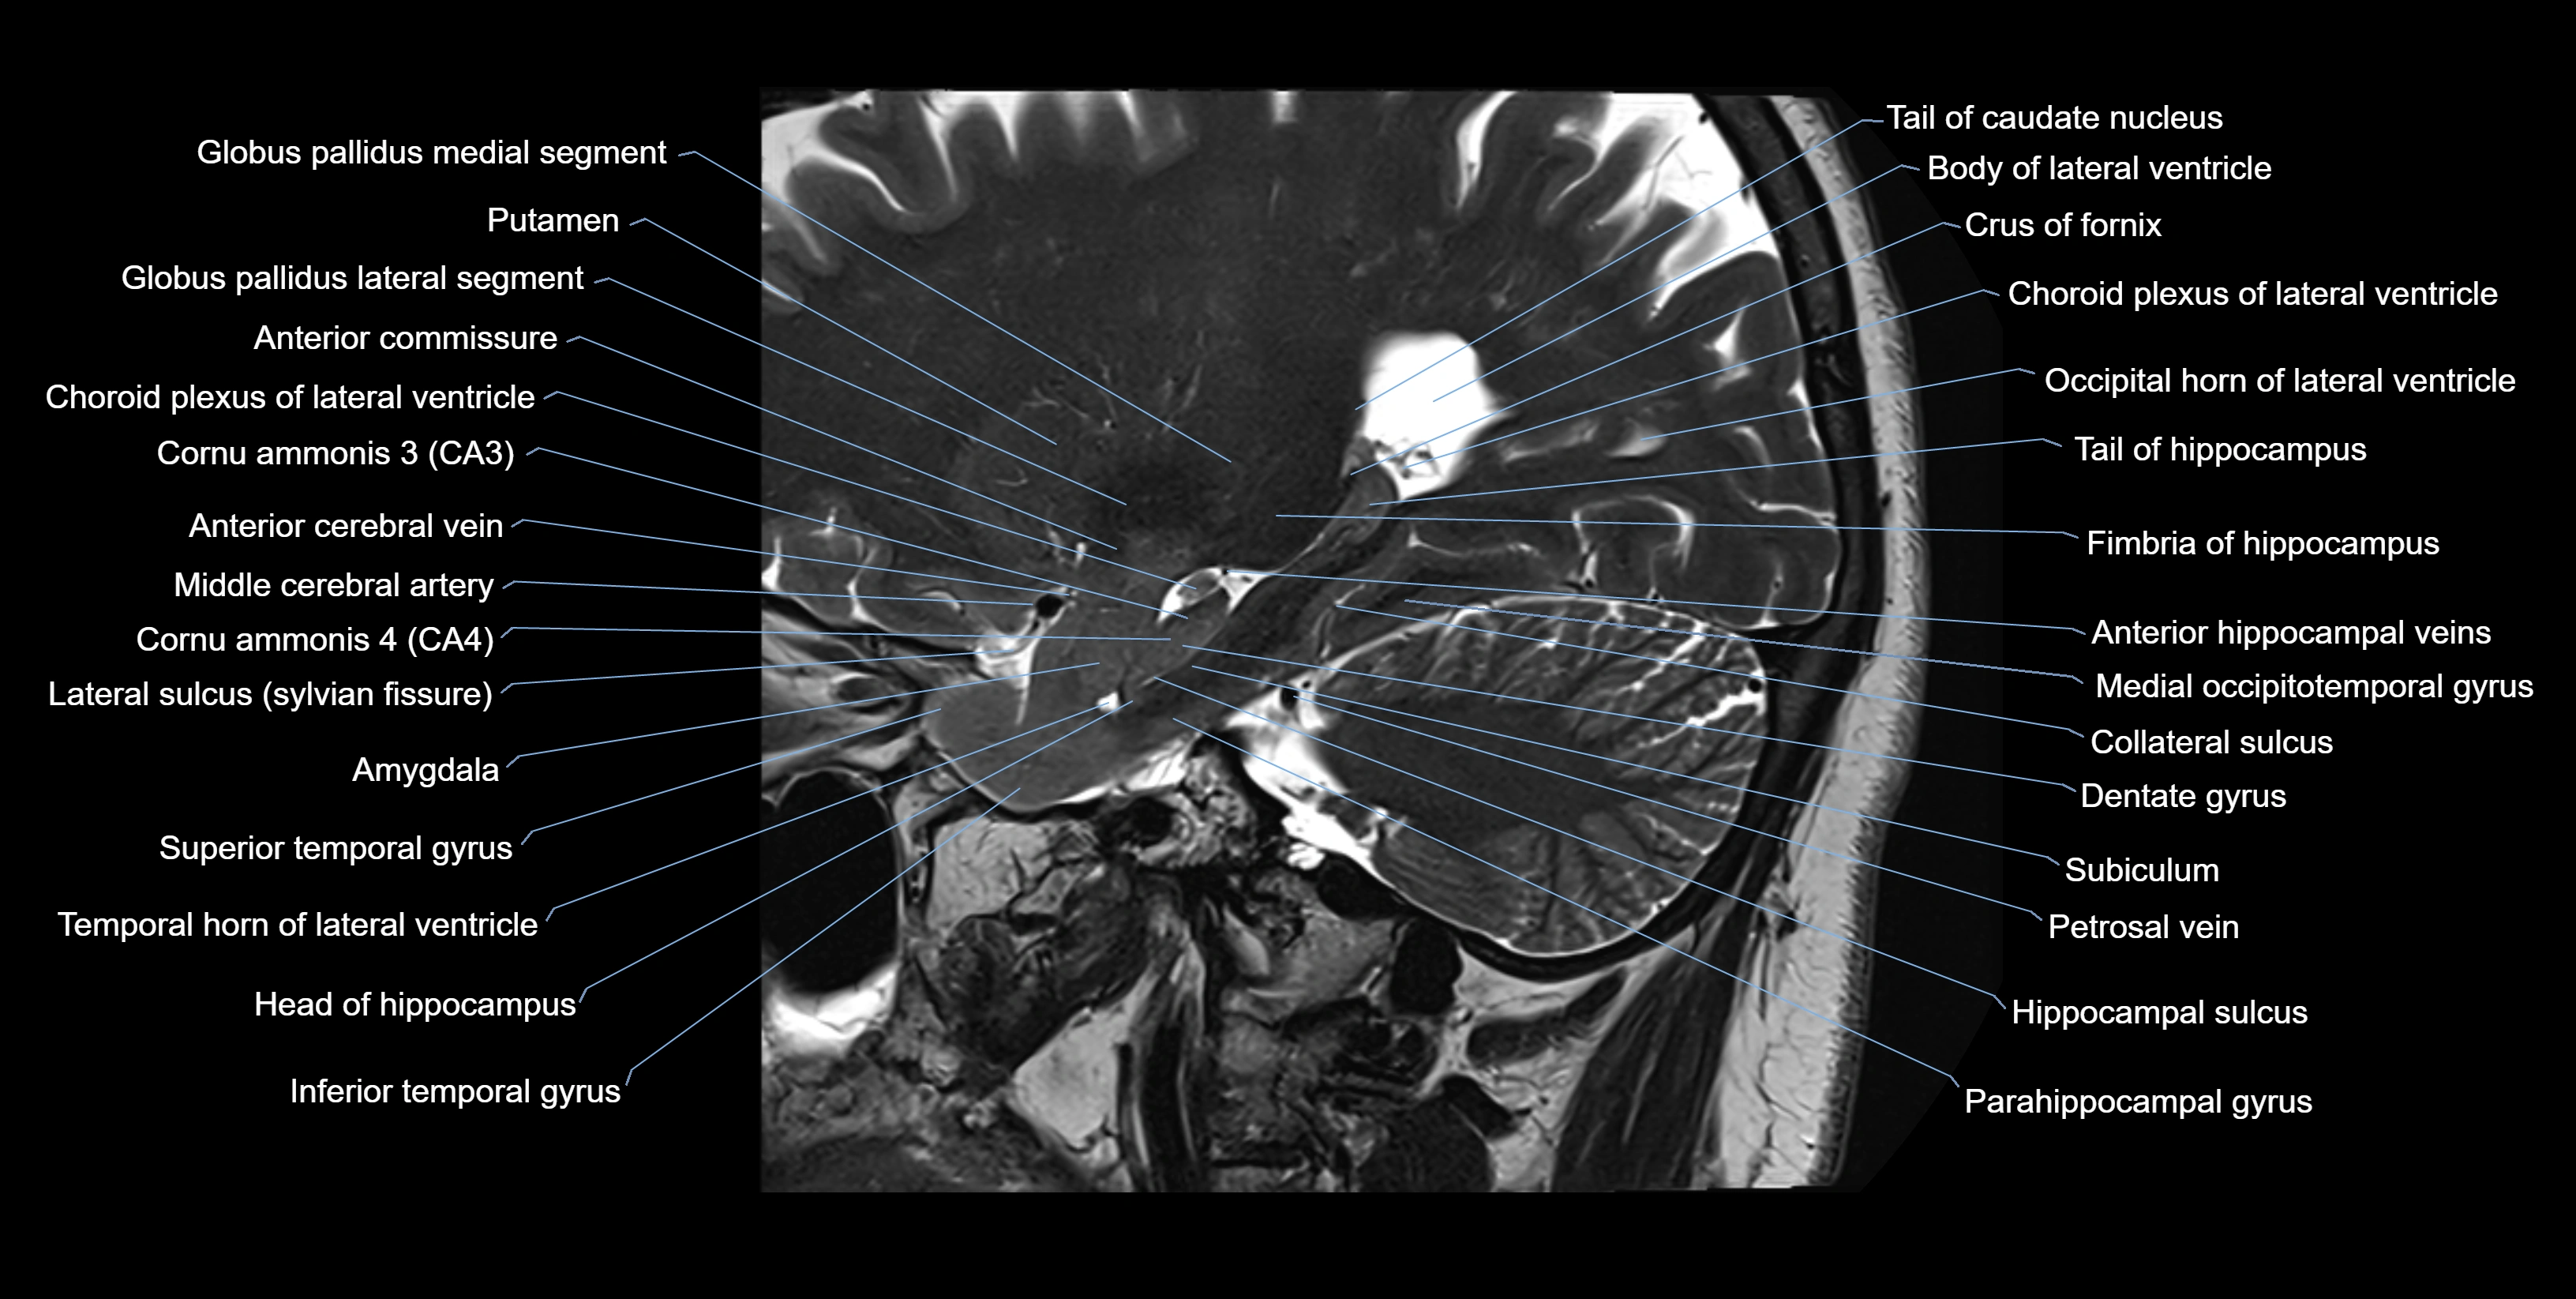

Alveus of hippocampus

The alveus of the hippocampus is a thin, white matter layer covering the superior (ventricular) surface of the hippocampus within the temporal horn of the lateral ventricle. It consists of myelinated efferent fibers arising primarily from the pyramidal neurons of the hippocampus. These fibers converge medially to form the fimbria of the hippocampus, which continues posteriorly into the fornix, forming a crucial part of the Papez circuit involved in memory consolidation and emotional processing.

The alveus serves as the initial output pathway of the hippocampal formation, linking it to other limbic structures including the hypothalamus, mammillary bodies, and cingulate gyrus. Because of its intimate relationship with the hippocampal head and tail, it is often evaluated in cases of temporal lobe epilepsy, hippocampal sclerosis, and neurodegenerative diseases.

Location and Structure

• Position: Lies on the ventricular (superior) surface of the hippocampus, beneath the ependyma of the inferior horn of the lateral ventricle.

• Composition: A thin sheet of myelinated axons derived mainly from hippocampal pyramidal cells.

• Course: Fibers run medially along the hippocampal surface to form the fimbria of the hippocampus, which curves upward and backward into the fornix.

• Relations:

• Superiorly: Ependyma and CSF of the temporal horn of the lateral ventricle

• Inferiorly: Pyramidal cell layer of the hippocampus (CA1 region)

• Medially: Fimbria and fornix

• Laterally: Temporal lobe white matter and parahippocampal gyrus

MRI Appearance

T1-weighted images:

• Alveus: Thin linear high signal band (due to myelinated fibers) overlying the hippocampal gray matter.

• Hippocampal gray matter: Intermediate signal intensity.

• CSF of lateral ventricle: Dark (low signal).

T2-weighted images:

• Alveus: Low signal line overlying brighter hippocampal gray matter.

• CSF: Bright hyperintense.